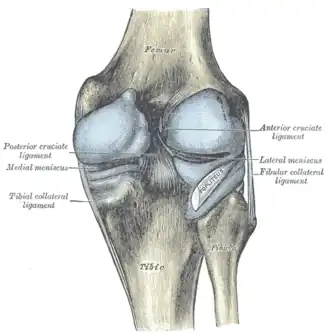

Left knee-joint, posterior aspect, showing interior ligaments. (Fibular collateral ligament labeled at center left.) | |